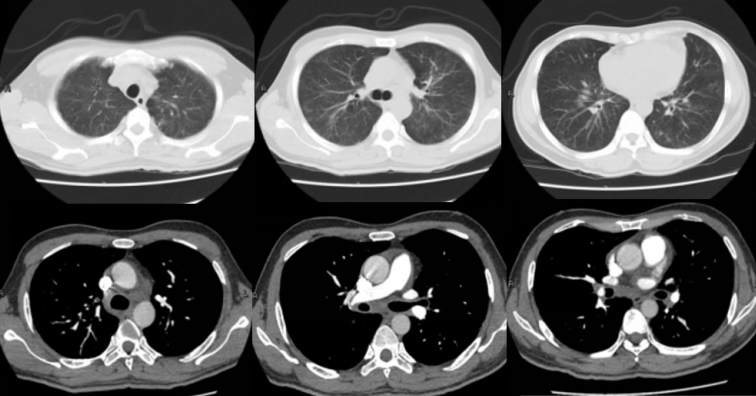

图4 右下后叶基底段开口黏膜活检结果:镜检为低分化腺癌,免疫组化:CK7(+),TIF-1(+),NapsinA(+),CK5/6(+),P63(-),P40(-),Cgd(-),Syn(-),CD56(-),ALK(D5F3)(+),ALK-N(-),符合低分化腺癌12月14日起,患者气促开始好转,咳嗽、咳痰减轻,复查胸片可见肺部吸收改善,12月16日胸片明显好转(图5),氧合指数升至203 mmHg,逐步减低Airvo支持参数,12月18日患者气促基本缓解,查血气提示氧合指数484 mmHg,改为鼻导管吸氧,复查胸部CT提示双肺病变明显减轻(图6),12月19日患者体温稳定,感染指标及胸片好转,亚胺培南降阶梯为哌拉西林他唑巴坦钠4.5g q8h联合替考拉宁抗感染治疗,12月20日患者无明显咳嗽、咳痰及气促,好转步行出院。

图6 胸部CTA(2017-12-17)

注:双肺弥漫性磨玻璃影及结节影较前明显好转;多发肺动脉栓塞,较前稍减少;双侧锁骨上窝、纵隔、双肺门多发淋巴结肿大,较前减小。出院诊断:①双肺弥漫型肺泡癌并全身多发淋巴结转移;②双肺社区获得性肺炎;③左肺动脉栓塞;④右侧颈静脉、右侧锁骨下静脉、右侧无名静脉血栓。